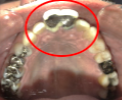

Before

【抜歯後】